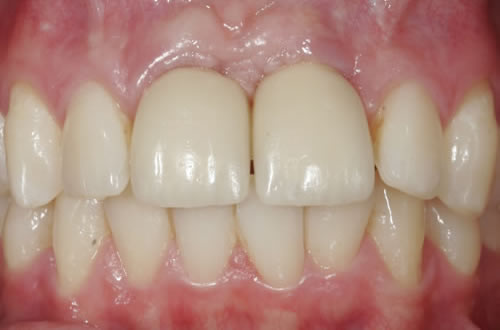

Eine besondere Herausforderung ist die Oberkieferfrontzahnregion. Der Wunsch nach einem perfekten Resultat ist geradezu selbstverständlich. Jeder möchte große, weiße Zähne und ein gesundes, reizloses Zahnfleisch besitzen (Abb. 3.30).

Abb. 3.30: Perfektes Resultat einer Versorgung.